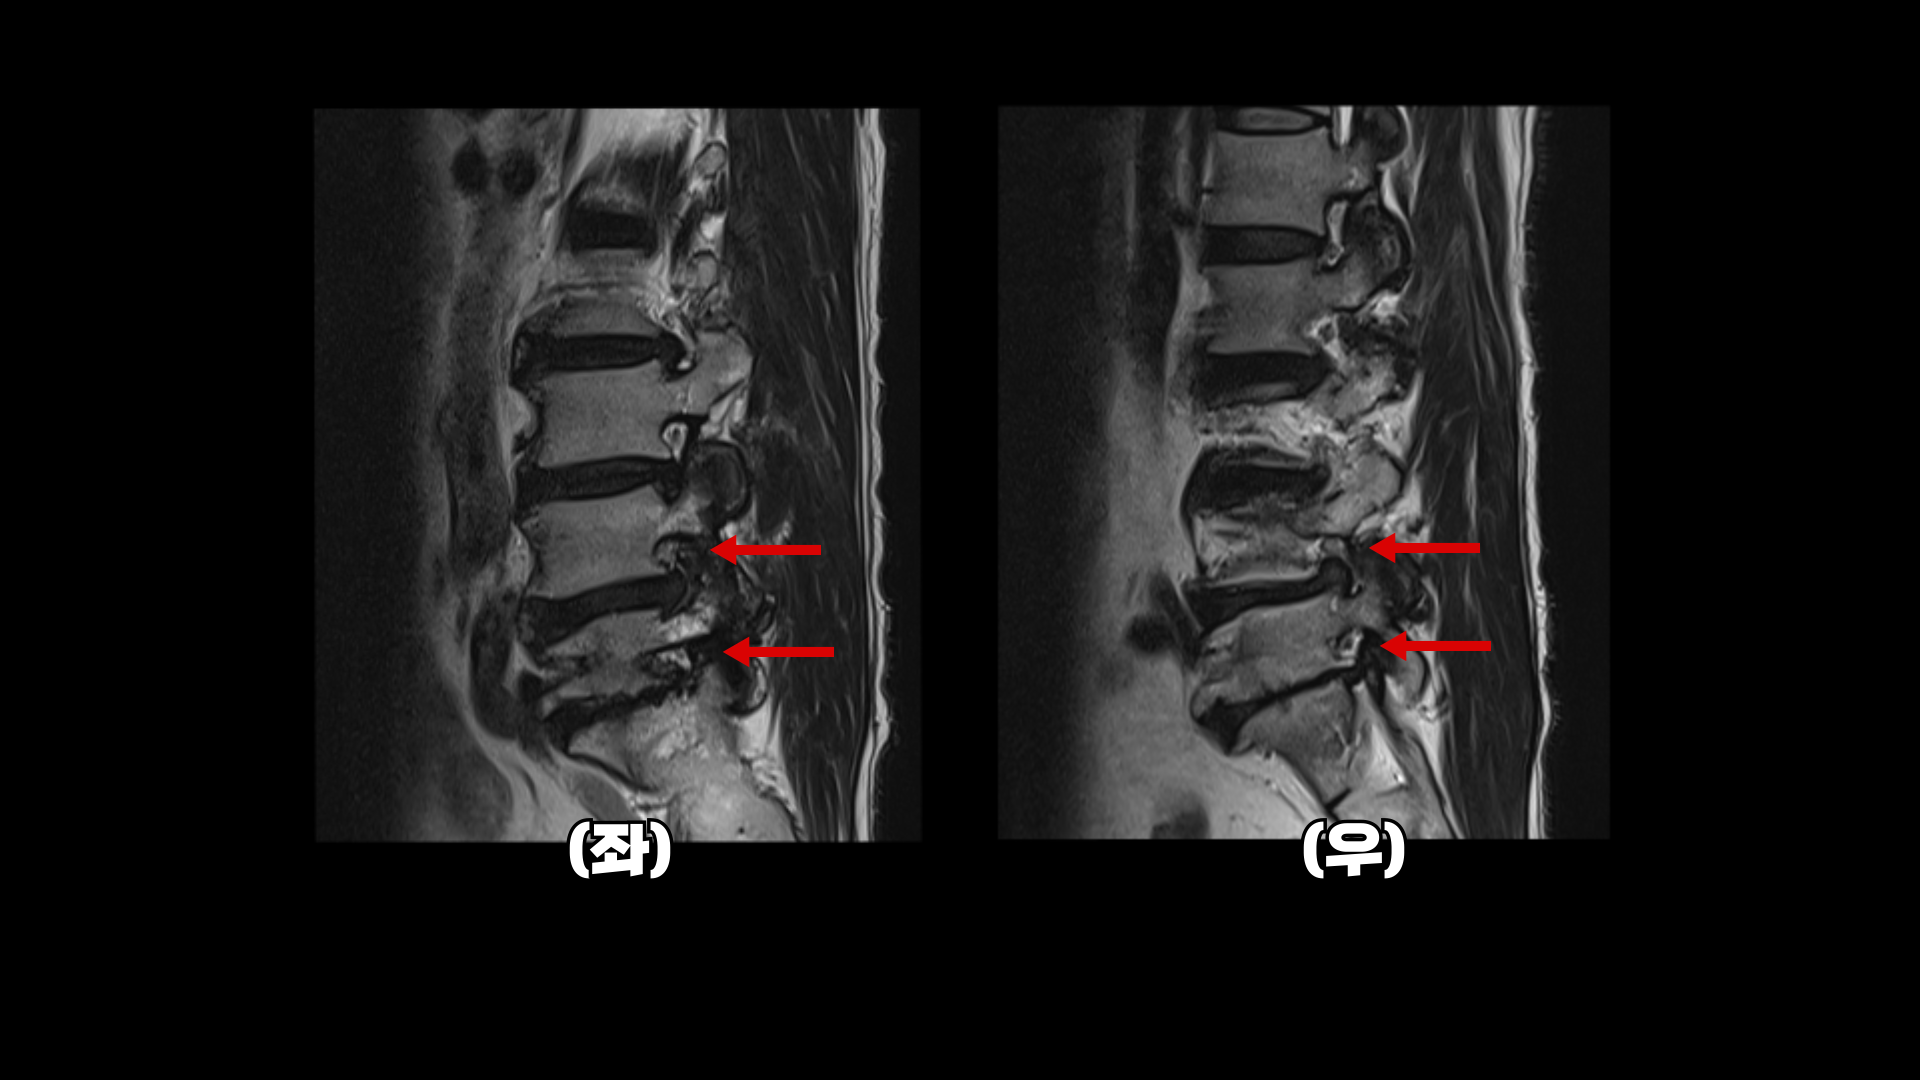

이분 MRI를 보면 네 마디에 퇴행성 디스크가 있고

두 마디에 중심성 협착이 있고

좌우로 나가는 신경구멍이 디스크와 협착으로 많이 좁아져 있습니다.

이분의 허리 MRI를 보면 2016년에 찍은 MRI와 2024년에 찍은 MRI가 있습니다.

이를 비교해보면 오른쪽, 왼쪽 다리의 마비 증상과 방사통의 원인인 걸로 추정되는 4번 5번과 5번 1번의 좌우 신경구멍이 비슷한 정도로 막혀 있습니다. 2016년과 2023년의 허리의 신경구멍이 좁아진 정도와 협착 정도는 비슷한 겁니다.